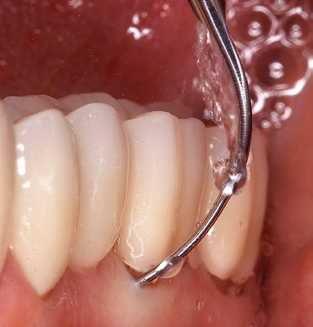

Of course, the use of instruments for mechanical removal of the biofilm is a central component of SPT and thus of primary significance. Consequently, the SPT workflow comprises both supragingival and subgingival cleaning. In our concept, a combination of hand instruments and machine cleaning has proven advantageous. A number of options are available for the mechanical procedures: sonic devices, ultrasonic devices and powder jet devices.

Good illumination of the working field facilitates the process considerably. The system used by the authors achieves this thanks to a 5x LED ring integrated in the handpiece. Naturally, a range of working tips for different indications is also offered. A straight, universally employable tip is the basic instrument required for machine cleaning of natural teeth (Fig. 5a and b). Curved tips, which allow access to exposed furcations, are also available for hard-to-reach areas in the posterior region (Fig. 6).

Of course, working tips for the cleaning of implant surfaces are also indispensable for SPT in patients fitted with implants. The implant cleaning attachment on the system used here is characterised by its tapered, hexagonal design. This design allows light, atraumatic penetration of the peri-implant pocket and displays a good cleaning performance (Fig. 7).

Fig. 4: Flexible probes with millimetre markings are recommended for the probing of dental implants (e.g. Colorvue Kit PCV11KIT6, Hu­Friedy). – Fig. 5a and b: A straight working tip (1P, W&H Dentalwerk Bürmoos GmbH) is a suitable instrument for use on all natural teeth. – Fig. 6: Curved working tips (3Pr/3Pl, W&H Dentalwerk Bürmoos GmbH) lend themselves to the processing of difficult-to-reach areas of the tooth and root surfaces (e.g. furcations). – Fig. 7: The tapered, hexagonal implant cleaning tip (1I, W&H Dentalwerk Bürmoos GmbH) permits atraumatic and efficient cleaning of the crown and abutment surfaces. – Fig. 8: Titanium and carbon curettes are suitable instruments for the manual cleaning of the implant surfaces.